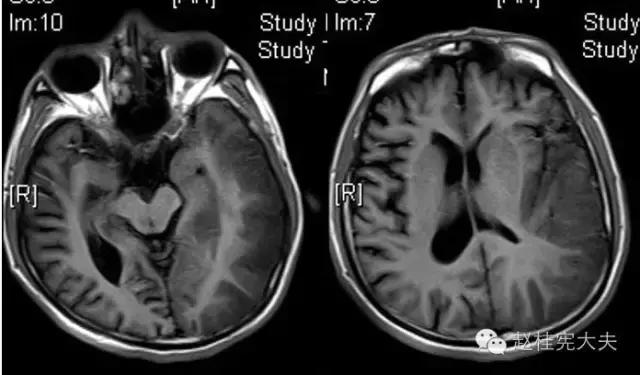

完善检查,头颅MRI回报:左侧颞顶枕叶急性梗死灶。

当看到磁共振片子的时候,我知道,我们轻忽了一些东西......

患者的磁共振影像不符合脑血管病的血供分布,跨了大脑中动脉和大脑后动脉范围,且病灶偏皮层分布。大脑前、中、后动脉血供分布(横断面)见下图